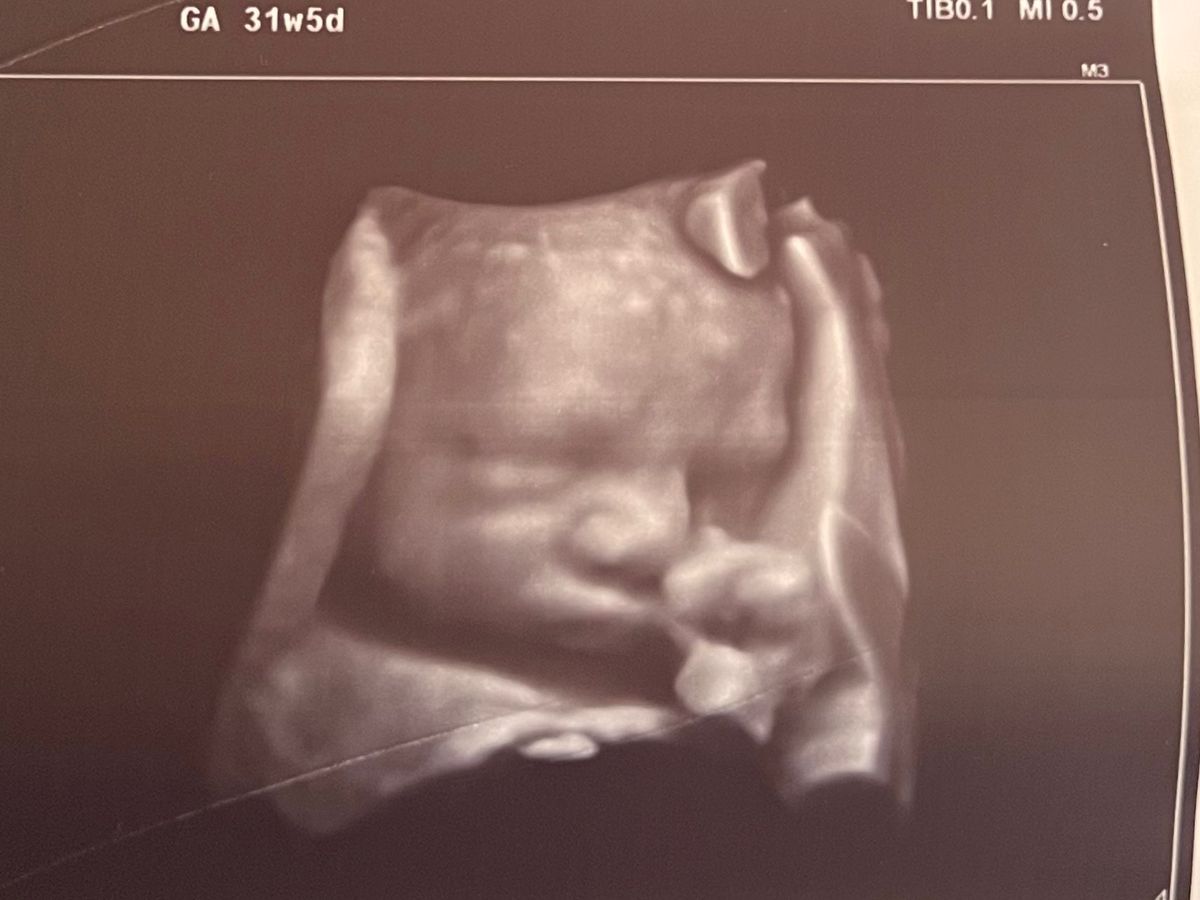

Hello everyone, my name is Cait. I am writing on behalf of my older sister Chelsey and my nephew Oliver. Chel is 32 weeks pregnant with Oliver. Oliver was diagnosed with Congenital Diaphragmatic Hernia (CDH). This means while growing in utero, a portion of his chest cavity never closed, causing his organs to push upwards through this opening, pushing against his heart. He also has an underdeveloped lung, which means he will need to be on an ECMO machine once he is born.